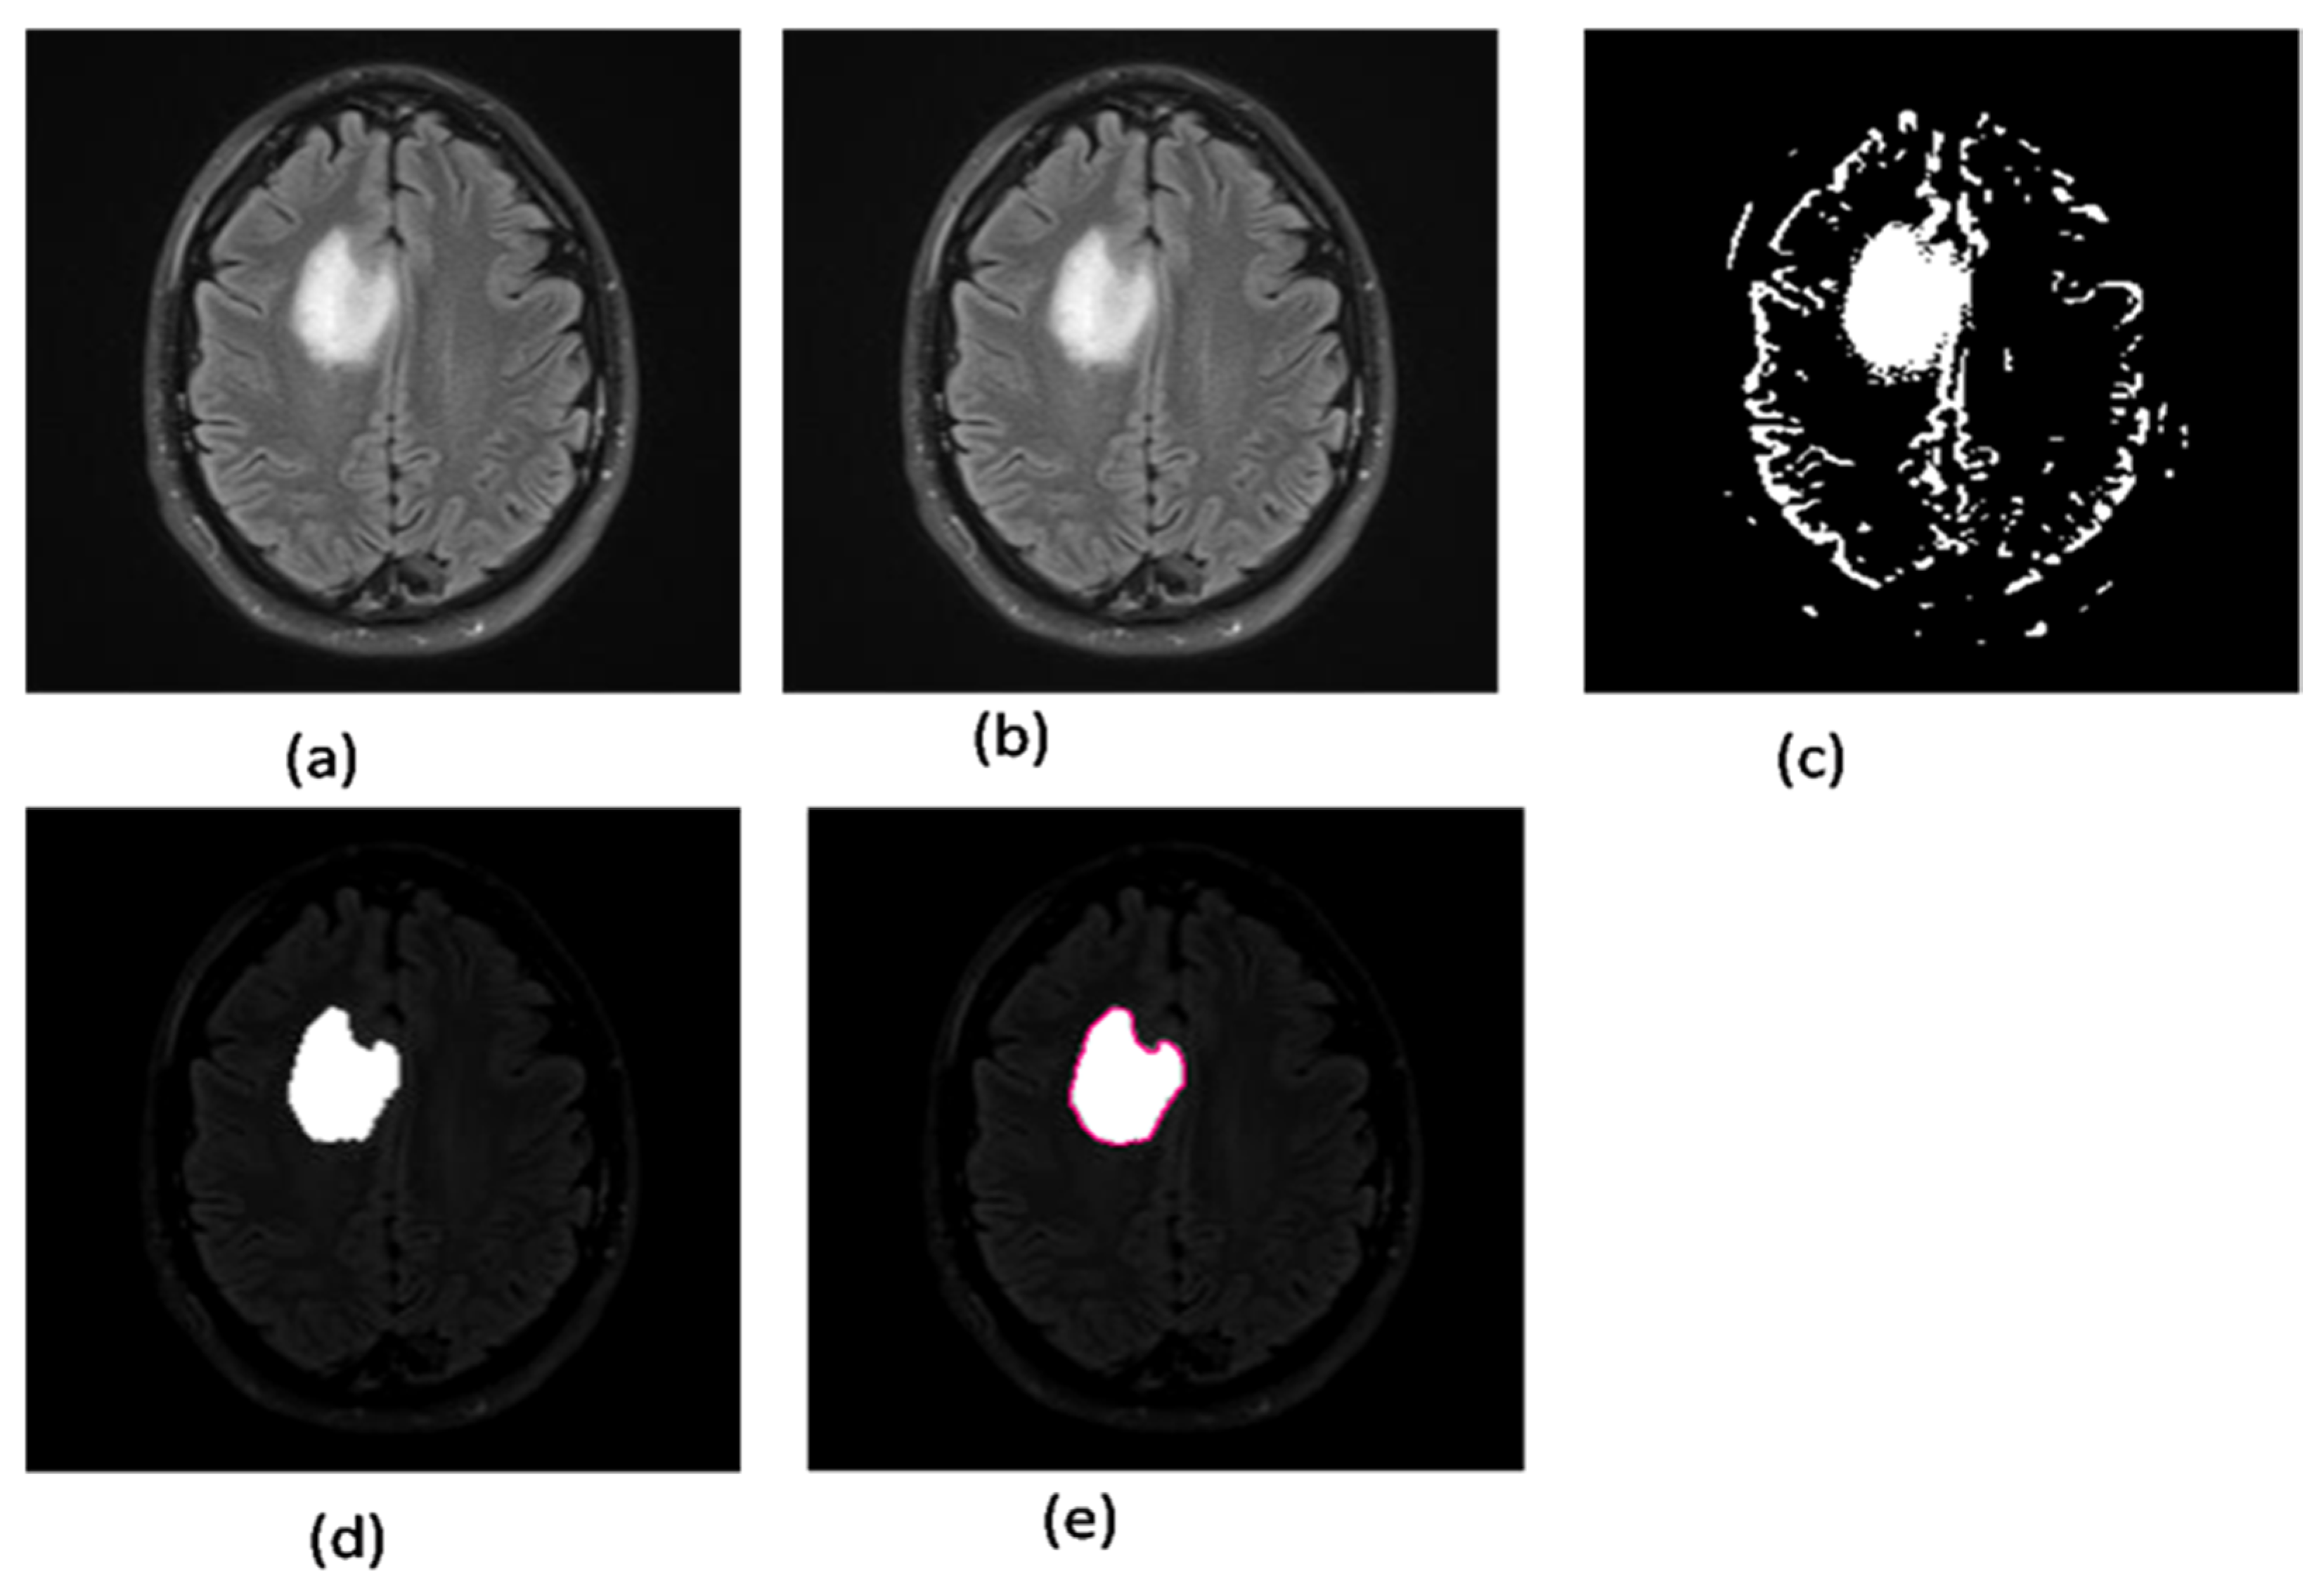

2.2.7. Area Segmentation using Watershed Algorithm

2.2.8. Region Masking and the Separation

2.3. Proposed a Colorized Method for Masked Area Colorization